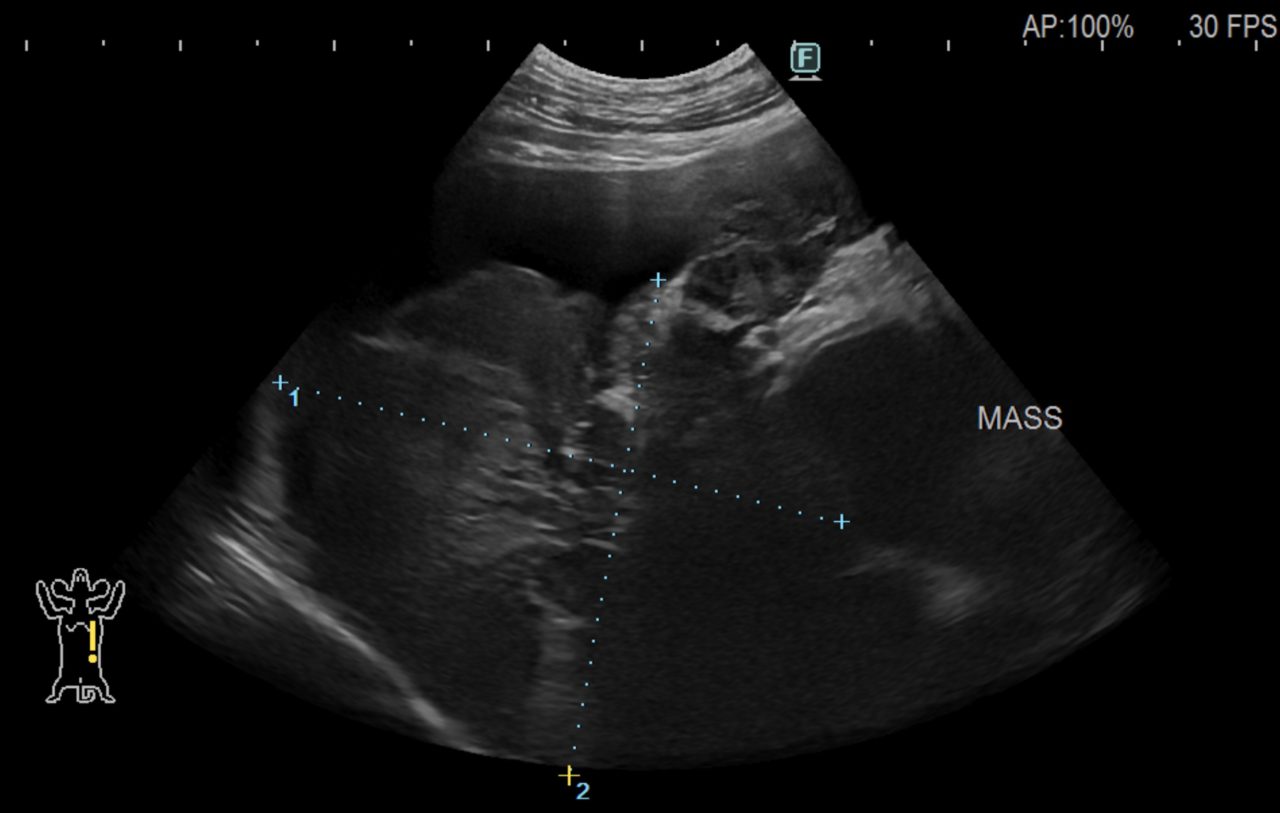

この患者さんは心嚢水が450mlも溜まっており、出血の原因と考えられる巨大な腫瘍が心臓に見つかりました。